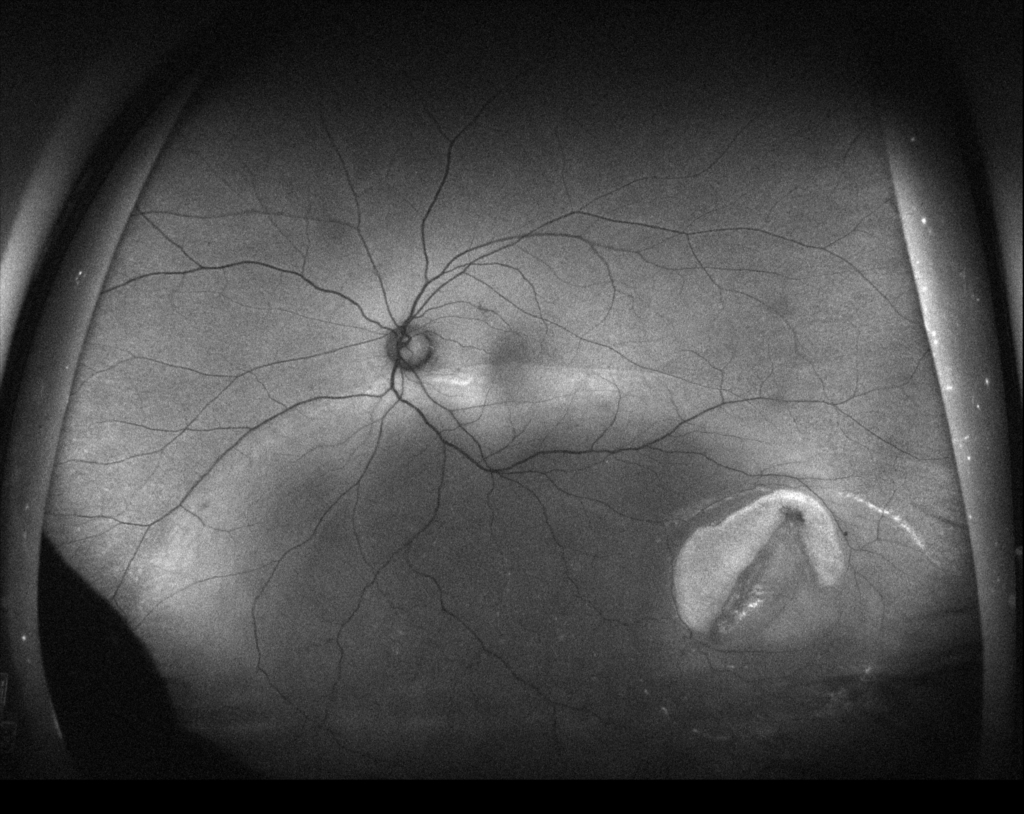

3時から8時に黄斑剥離を伴う胞状網膜剥離があり、4時に弁状裂孔がみられる。

12時から2時に格子状変性がみられる。